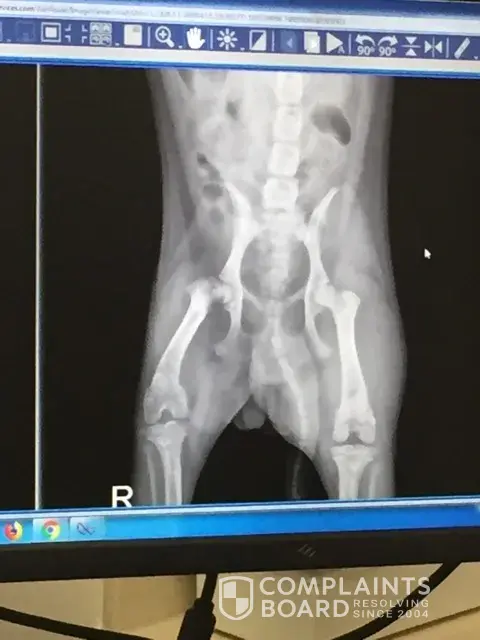

DKV Rottweilers - sold us a sick puppy with an estimated life span of 3 years.

We picked our purebred import rottweiler puppy from dkv rottweiler in ga on 7/20/19 and drove all the way back to nyc. On 7/22/19 we were told that our puppy had a level iii/vi heart murmur. We immediately notified dkv of the situation and they spoke with our vet. They contributed the heart murmur from traveling, new smell, new environment etc. On 08/19/19...